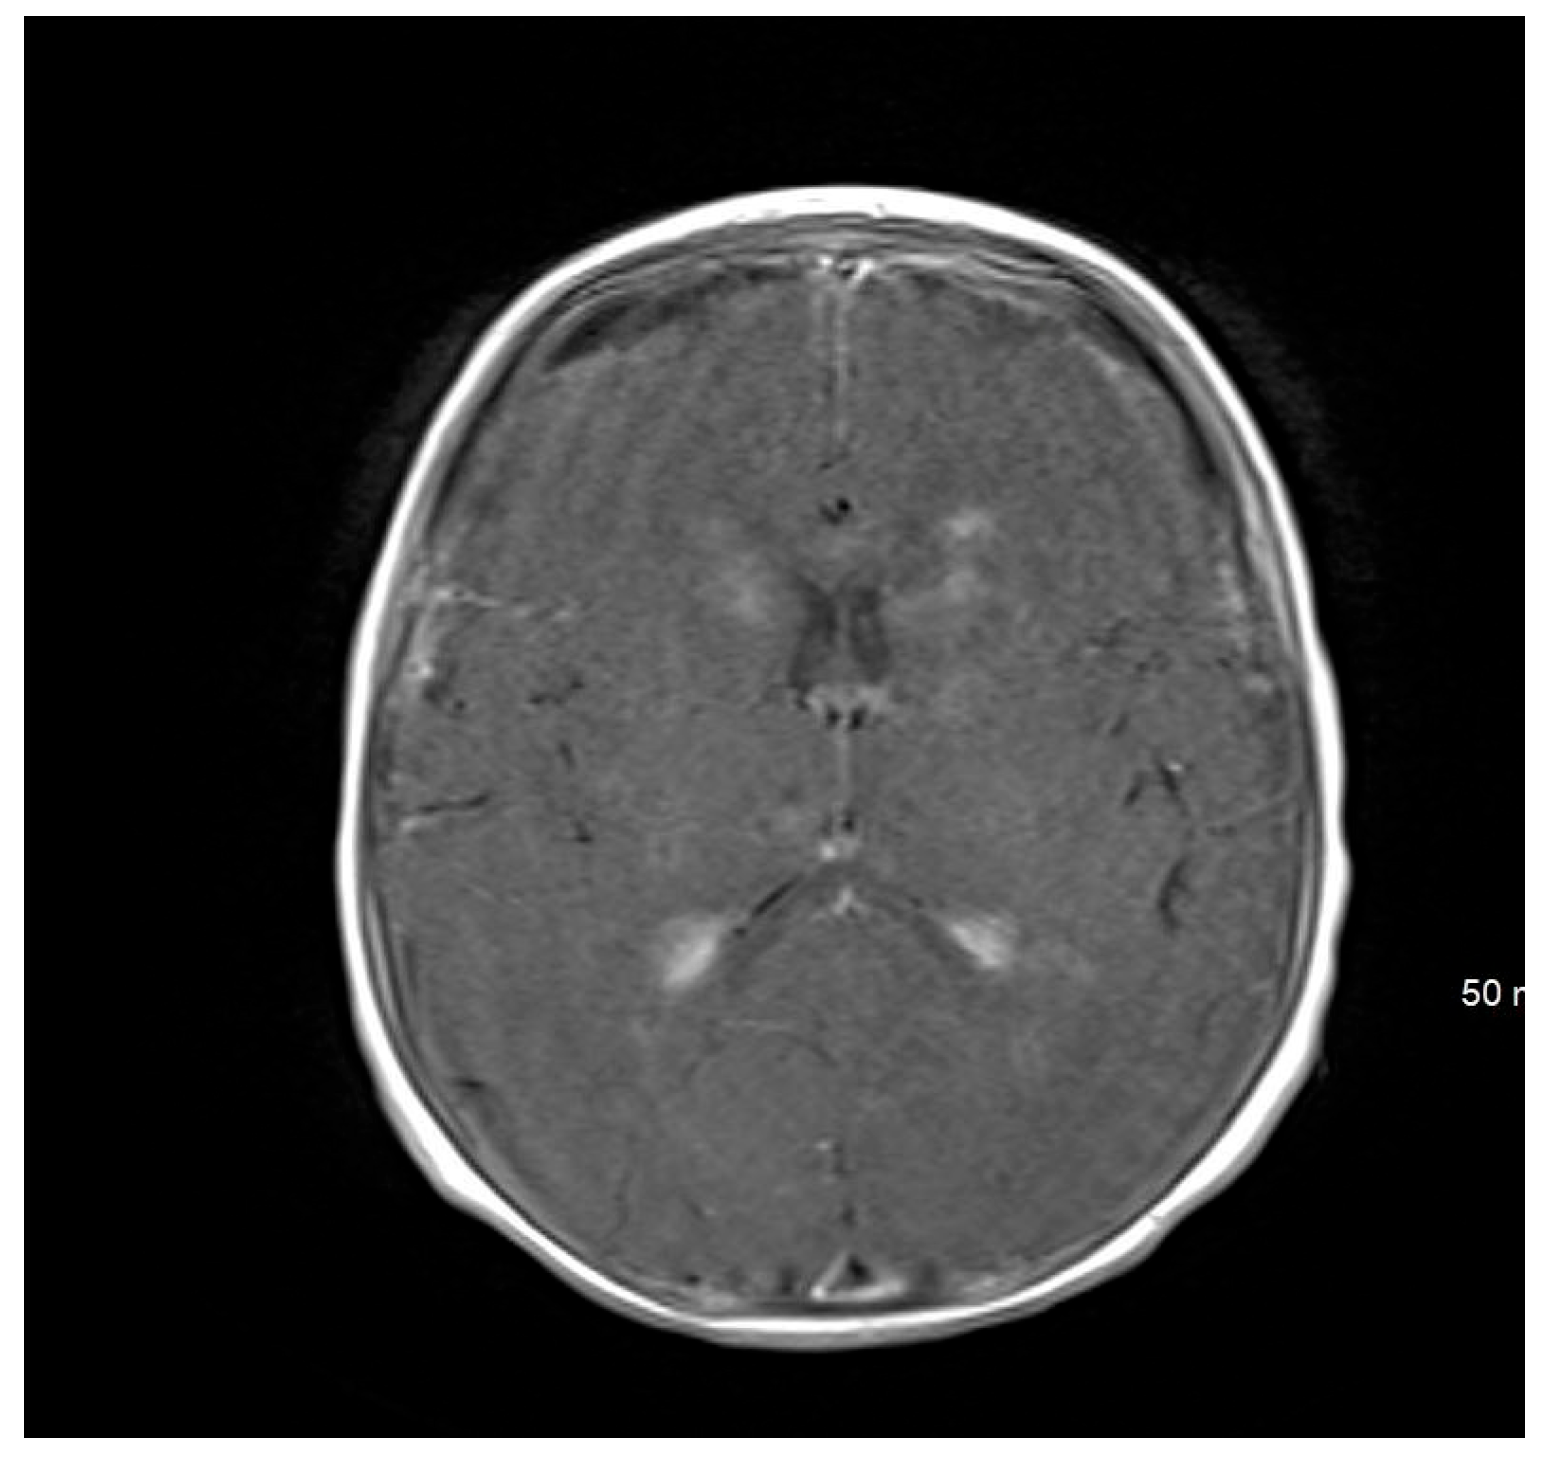

Brain magnetic resonance imaging (MRI) findings on 24 September 2022, were indicative of a hypoxic–ischemic insult, demonstrating hypoperfusion in the watershed areas of the periventricular white matter. Meningeal enhancement was consistent with meningitis, accompanied by bilateral basal ganglia and thalamic infarctions. The possibility of underlying abscesses or cerebritis could not be excluded.

An MRI repeated on 11 November 2022, after 7 weeks of treatment, showed interval resolution of the abscesses and subdural empyema, with resolution of leptomeningeal disease. Expected changes were observed, including brain volume loss and periventricular leukomalacia, with the previously described foci of enhancement. The internal auditory canals appeared unremarkable (Figure 1, Figure 2, Figure 3, Figure 4 and Figure 5).

Figure 1. MRI brain scan showing the watershed area infarction.